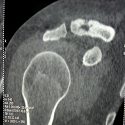

Kyste synovial postérieur lombaire

Mohamed Badaoui, Abdennasser El Kharras

PAMJ. 2016; 24: 173. Published 29 June 2016